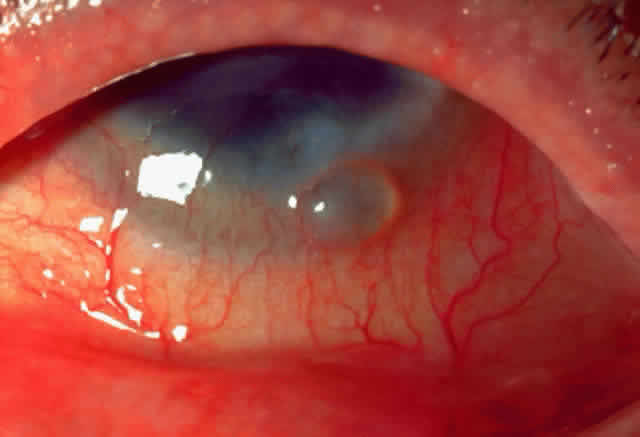

Limbal vernal begins as a thickening and opacification of the limbus. Limbal nodules appear as gelatinous, elevated lesions that may seem to coalesce and become confluent. Horner-Trantas' dots are small white elevated lesions that appear at the apices of limbal excresences that consist of desquamated epithelial cells and eosinophils (Fig. 4). Mixed vernal is a combination of limbal and palpebral lesions.

Fig. 4. Limbal vernal: Horner-Trantas' dots and elevated gelatinous lesions.